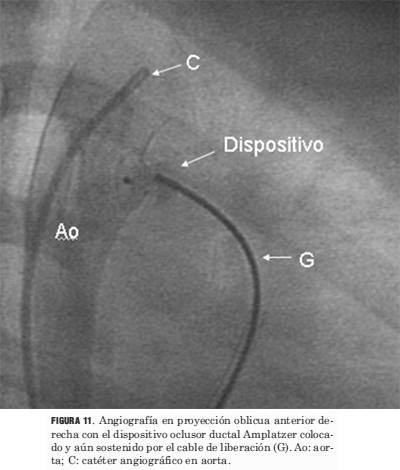

Los procedimientos de cierre del ductus se llevaron a cabo sin el uso simultáneo del ecocardiograma (figuras 9, 10, 11, 12 y 13).

Figura 11. Angiografía en proyección oblicua anterior derecha con el dispositivo oclusor ductal Amplatzer colocado y aún sostenido por el cable de liberación (G). Ao: aorta; C: catéter angiográfico en aorta.